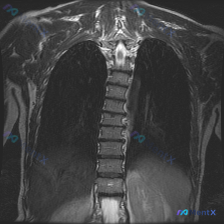

网上看到一张胸椎MRI T2序列冠状位影像,先放影像分析里的核心表现: - 胸椎椎体排列连续,骨髓信号均匀,没看到明显骨质破坏或水肿 - 椎间盘T2低信号,高度基本维持,冠状位没见明显侧方突出 - 脊髓信号均匀,硬膜囊形态连续,没见明确占位压迫 - 但冠状面能看到胸椎呈轻度向右侧弯畸形 用户标注的答...